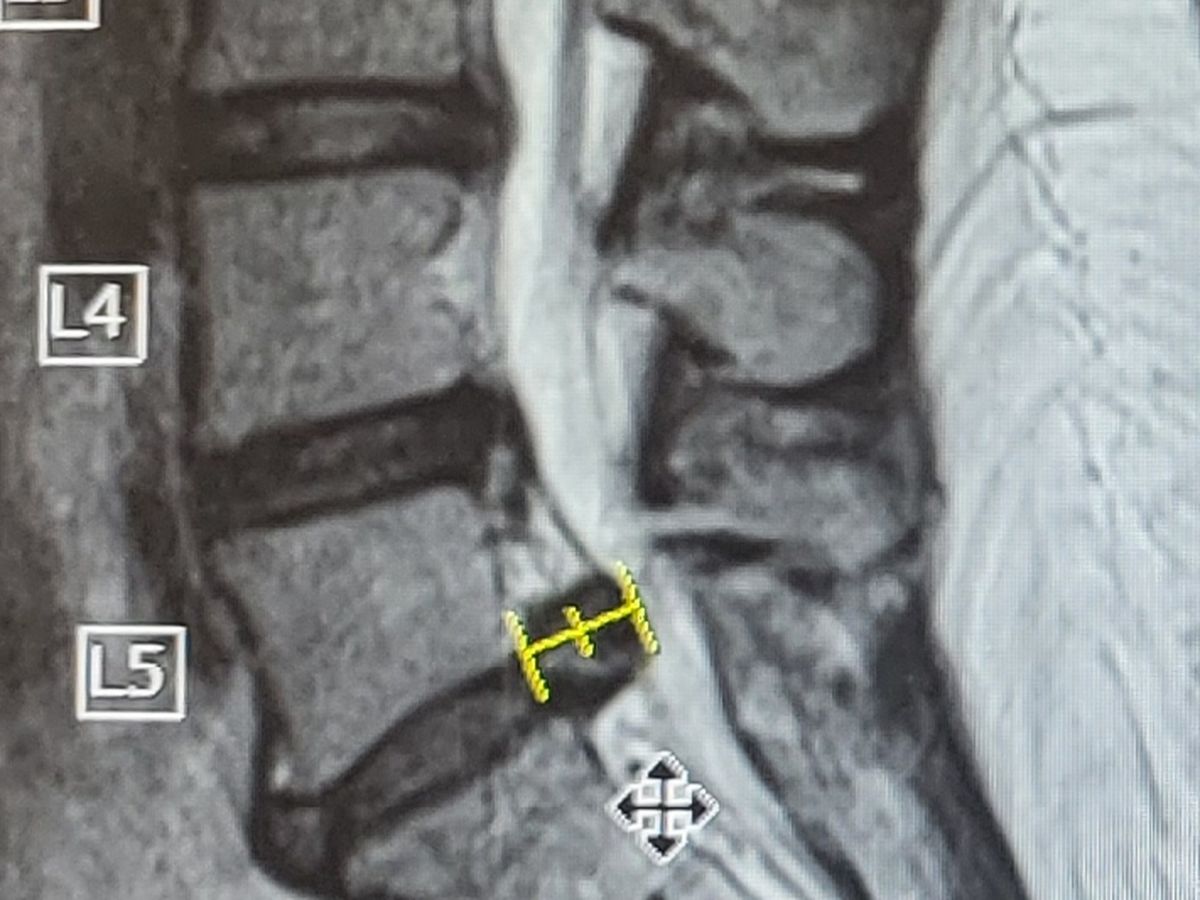

Last summer I injured my back and never fully recovered. For the last several plus months I've dealt with debilitating back and leg pain that's impeded my ability to work, connect with loved ones, and live life to my fullest expression.